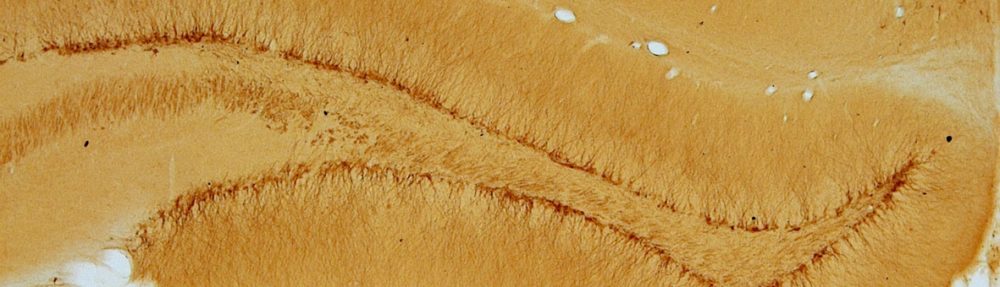

This interdisciplinary course integrates neurobiology and quantitative MRI (qMRI) to explore how brain structure and function can be objectively characterized. Through eight interactive sessions combining lectures, discussions, and student presentations, participants will connect imaging-derived biomarkers with underlying tissue structure and physiology.

The course emphasizes interdisciplinary learning, linking anatomy, physics, and clinical imaging to foster advanced understanding of brain organization and promote international academic collaboration.